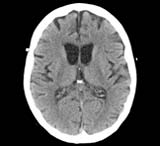

Erstmal ein paar Schädel CTs von Google...

Computertomographie (CT) des Großhirns eines gesunden älteren Menschen (a), eines Patienten mit Alzheimer-Demenz (b) und vaskulärer Demenz (c) (Abbildung aus: Alzheimer & andere Demenzen: Antworten auf die häufigsten Fragen, G. Krämer & H. Förstl, Trias Verlag, S. 145)

http://www.alzheimer-kompakt.de/alzheimer-erkennen-behandeln/diagnose.html (Archiv-Version vom 03.02.2011)